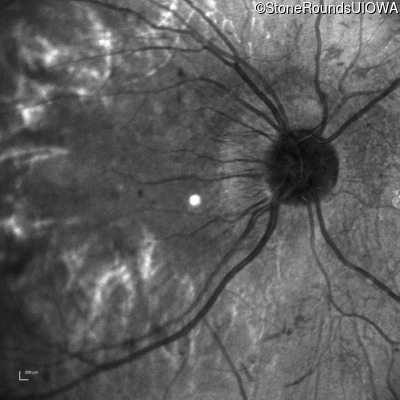

Infrared Fundus Photograph - Right - 20/200 -1

Exemplar

Infrared Fundus Photograph - Left - 5/160